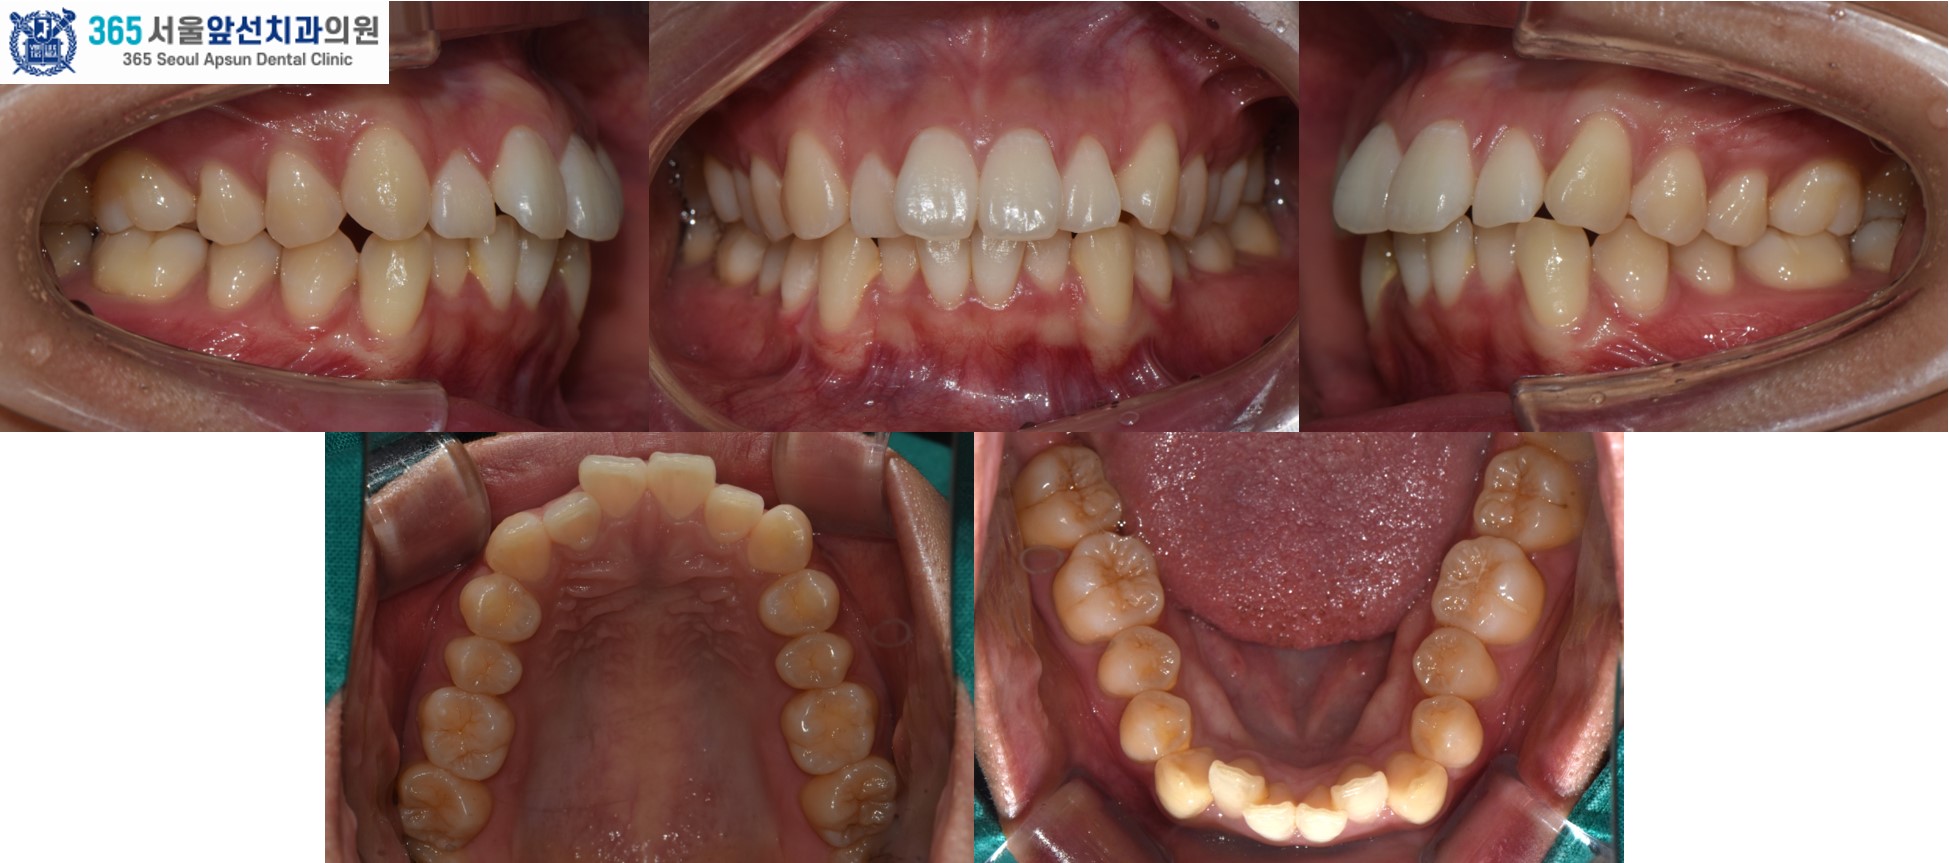

앞니의 비뚤한 치열을 고민으로 내원하신 20대 여성 환자 분의 증례를 소개드리겠습니다. 치료 전의 모습입니다. 상,하악 치열 각각 3.1mm, 2.9mm 의 필요 공간이 있는 중등도의 총생(Crowding)이 관찰됩니다. (그림2) 촬영일자 2025.02.25.

아랫니의 치열이 윗니의 치열보다 후퇴되어있는 2급 부정교합도 있었지만, 환자분은 2급 부정교합은 수정하지 않고 앞니의 치열만 가지런히 하기를 원하셔서 부분 교정으로 진행하였습니다. 이 경우, 2급 부정교합과 수평 피개는 잔존하게 됩니다. 부정교합의 정도에 따라, 치료계획을 좀더 간단하게 수정할 수 있습니다. 전체 교정과 부분 교정의 계획은 꼭 전문의와의 상담을 통해 결정하는 것이 좋습니다. ^^ (그림3) 촬영일자 2025.11.06.

치료 후의 모습입니다. 아랫니 치열은 약 5개월, 윗니 치열은 약 7개월의 치료기간이 소요되었습니다. 앞니의 치열이 가지런하게 배열되어 환자분도 만족하셨습니다. 미소 시 자연스럽고 단정한 인상으로 변화하였습니다. 앞니 부분 교정 증례의 치료기간은 4-9개월 사이로 정도에 따라 상이합니다. 부분 교정 관심 있으신 환자분들께서는 365서울앞선치과로 내원하셔서 교정 진단 받아보시길 바랍니다. 감사합니다!